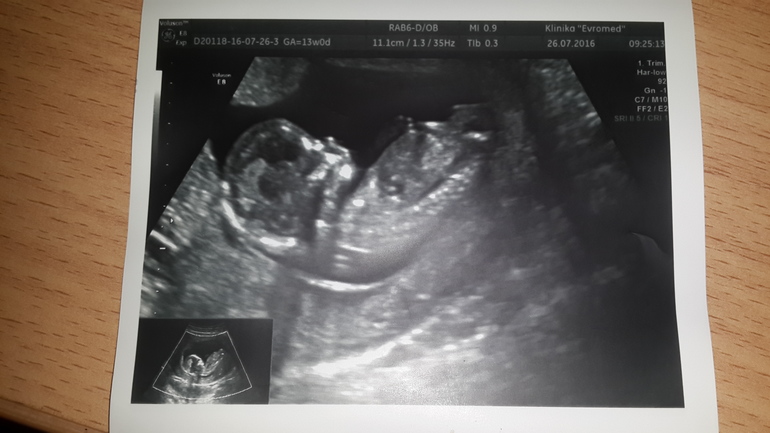

Беременность- 1 триместр ( только до 10 недель)Здравствуйте мои дорогие! Вот и прошло 13 недель! Первый свой скрининг решила делать в платном центре,т.к. по отзывам узи в ЖК не порадовало! Заранее узнала что не знаю за сутки есть жареное, сладкое,соленое и копченое,поэтому вечером покушала вареников и легла спать! Регистраторы подобрали время узи в 9.15 утра,а потом сразу кровь! На узи увидела как мой малыш активно дрыгает ручками и ножками (подвижный ребеночек),узистка показала ручки,ножки, и сердце...а в нем в левом желудочке синдром "гольфного мяча"....в целом все остальное в роде в норме. На прием к Г только 3 августа,поэтому пока переживаю,хоть и прочитала что этот синдром не является пороков. Тем не менее помогите расшифровать результаты пожалуйста(больше волнует кровь ). А еще мне сделали фото 4D (там простите какое то зло (это я любя конечно))! !!